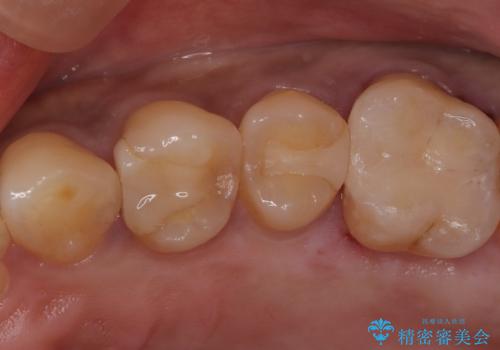

- 前医で治療された詰め物の部分に、定期検診で虫歯が見つかったため、セラミックインレーにて修復治療を行いました。

接着時にはラバーダム防湿を行っています。